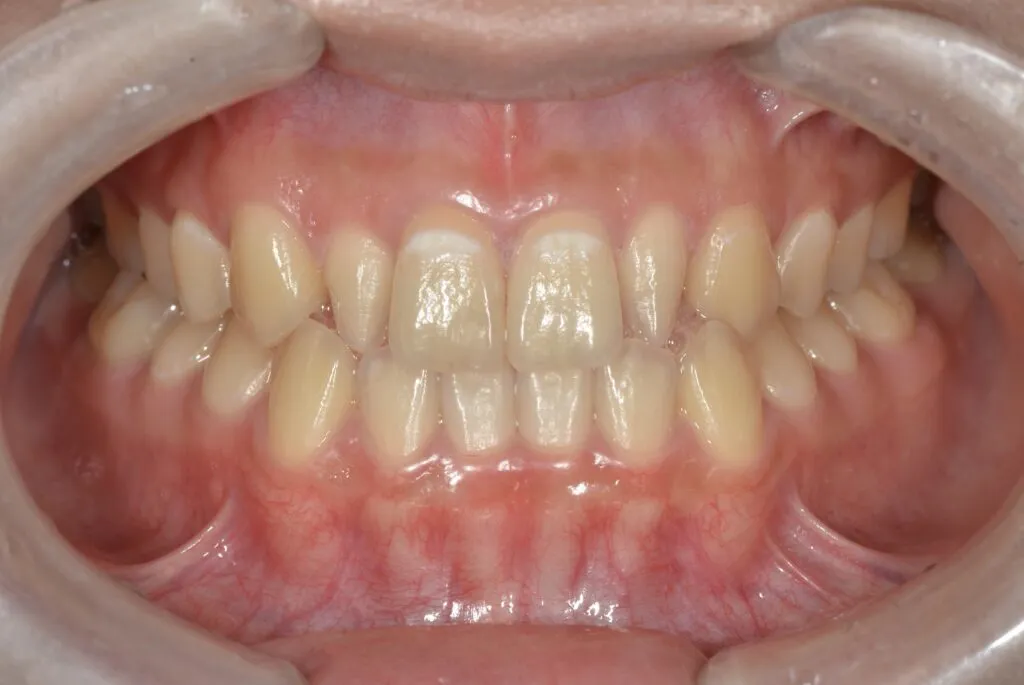

[症例2]

治療前は臼歯部は保険の冠のため金属色が目立ちます。上顎の前歯はセラミックですが、古いタイプの治療法ため裏側に金属が露出しています。

矯正治療後に部分被せも含めて全てセラミックで治療しました。

右下6番は歯を真ん中で分割して2本の冠が入っていましたが、抜歯してインプラントが入っています。

上下顎とも金属色の見えない美しい歯並びになりました。

- 治療期間:約1年

- 治療費:240万円

- 治療回数:26回